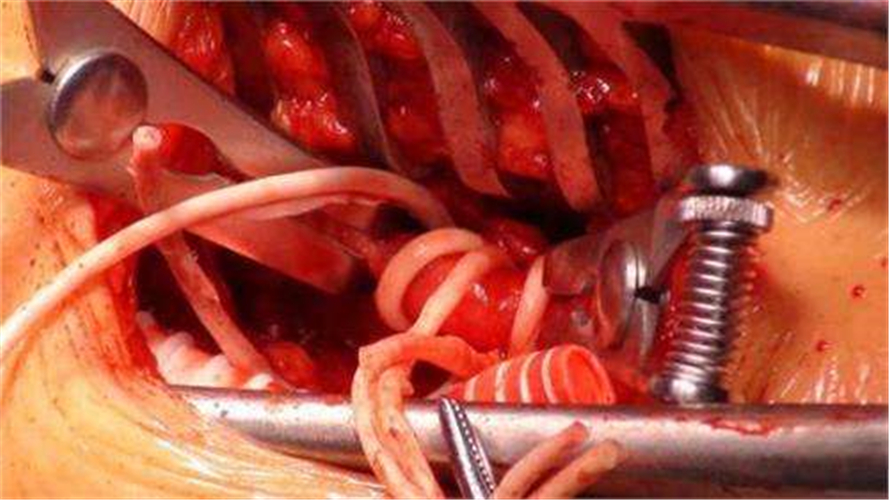

由高血壓腦血管痙攣引發的腦出血治療

血管狹窄引起腦血管痙攣手術

手術治療煙霧病引起的腦血管痙攣

手術治療腦血管痙攣

手術治療腦血管痙攣的

手術治療腦血管痙攣合併動脈瘤

腦血管痙攣手術中